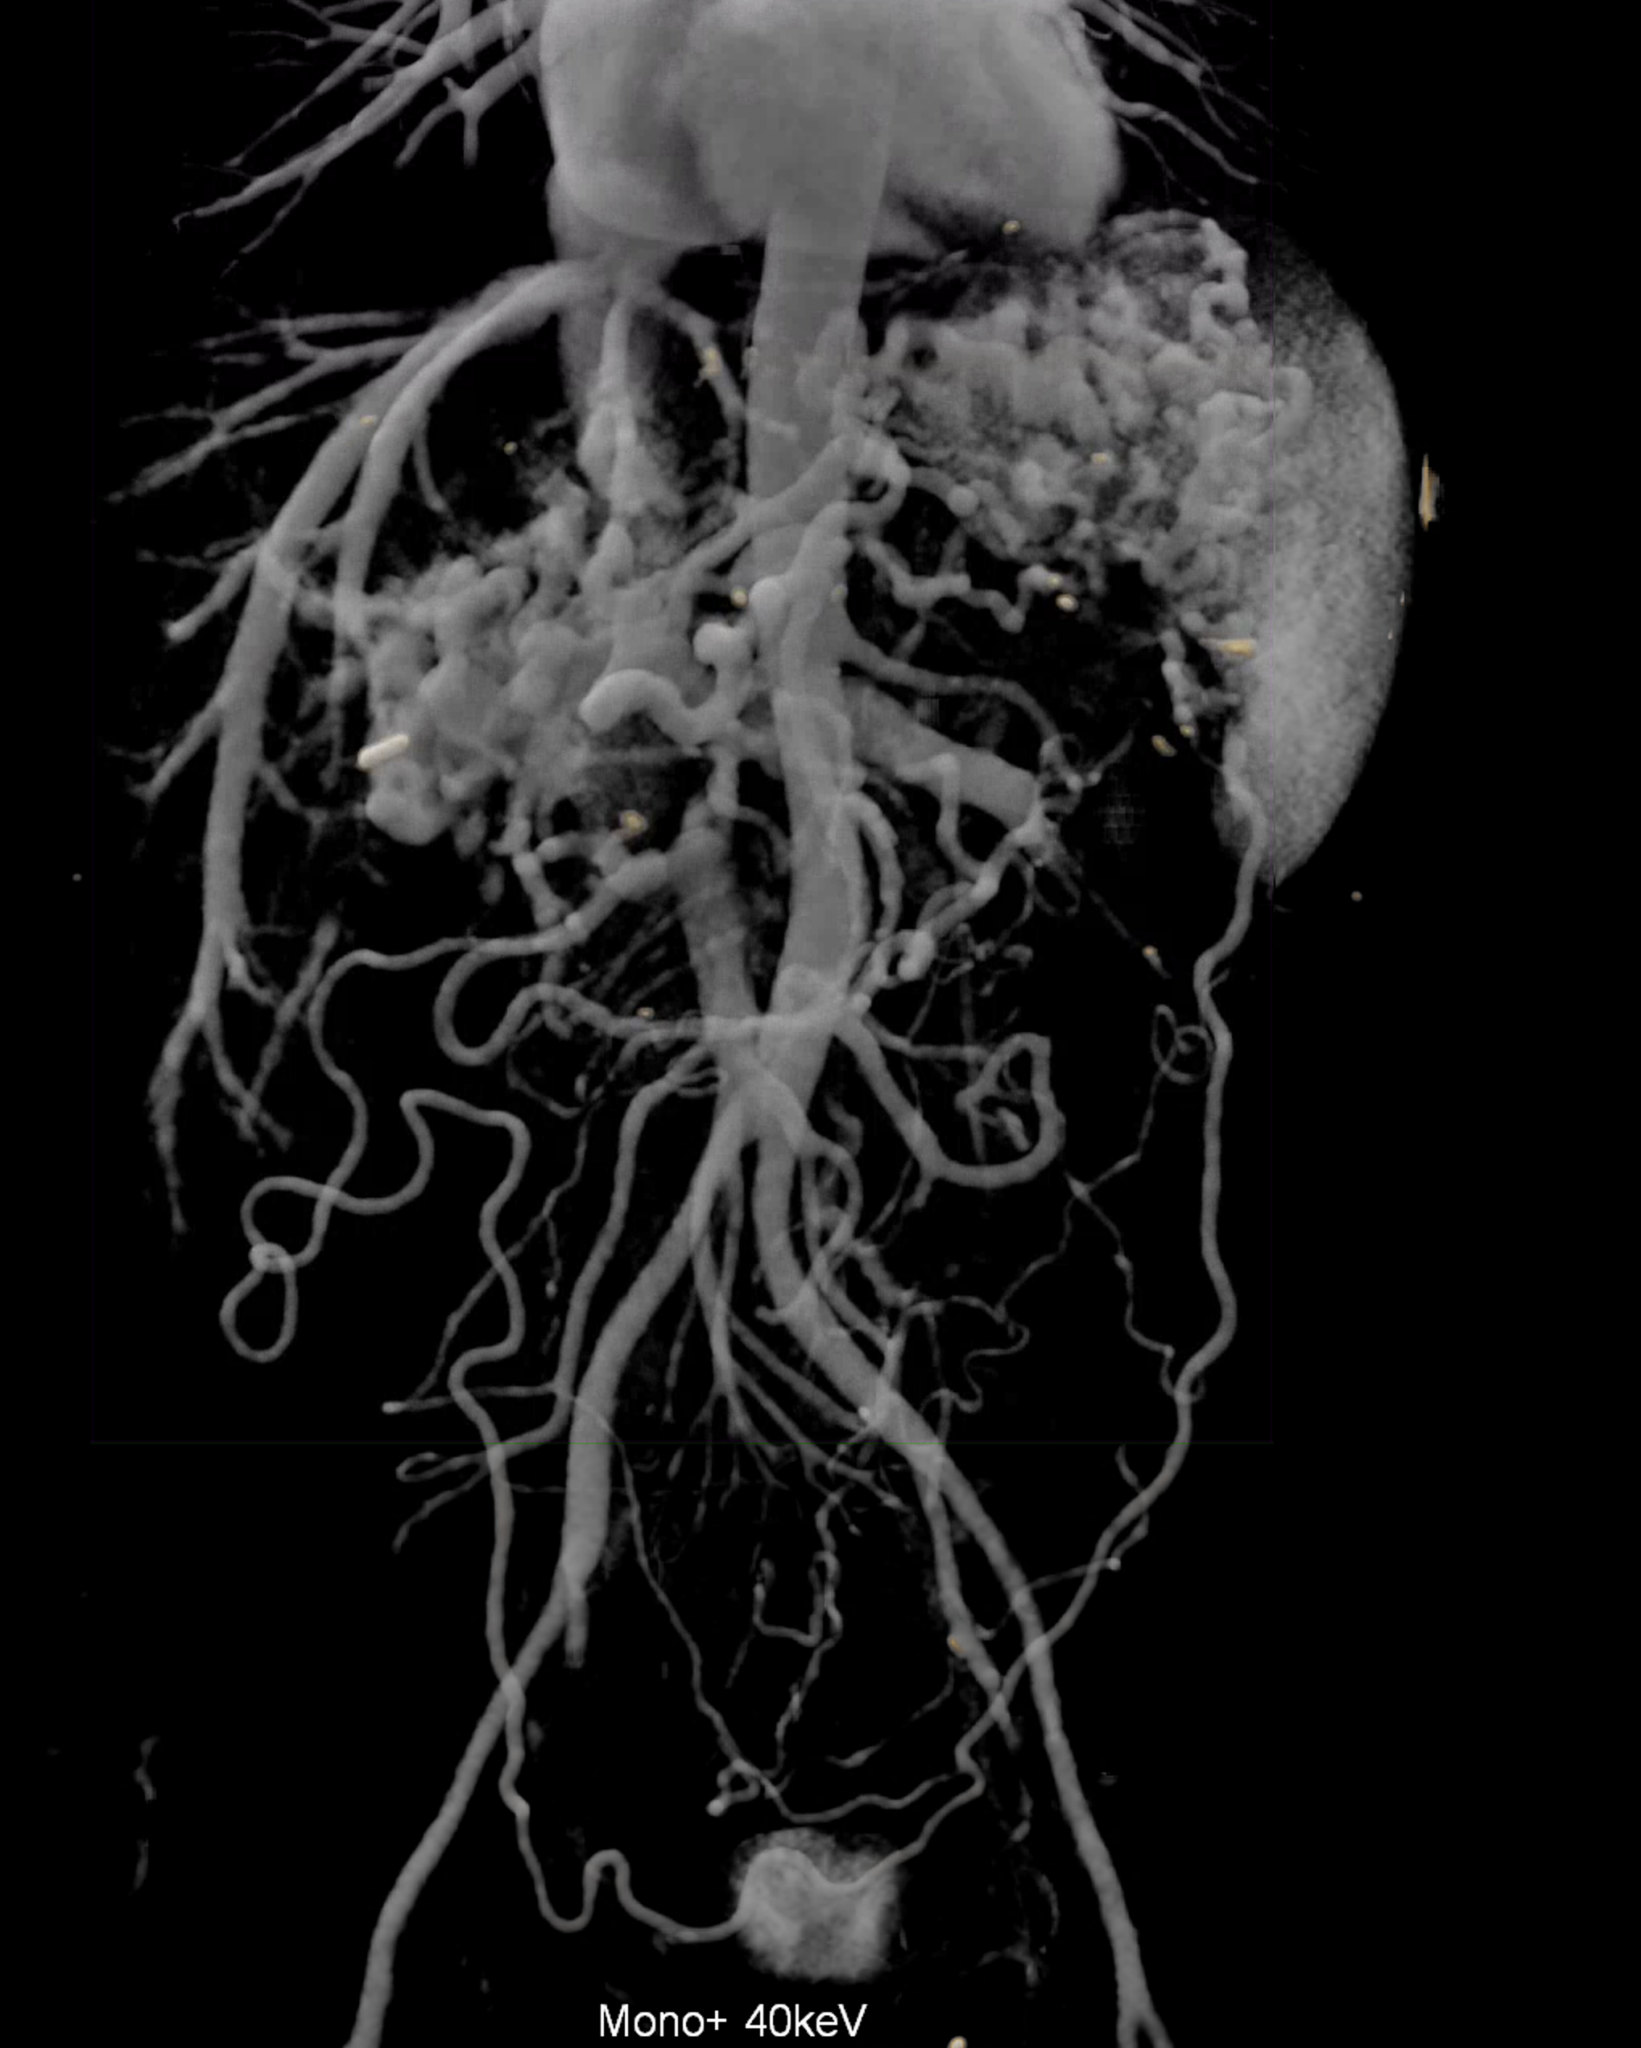

A patient with chronic pancreatitis and chronically occluded portal vein. The bile ducts have a significantly dilated wall, from the trunk, through the stump of the cystic duct, to the right and especially the left branch of the hepatic duct. At the same time, a large pseudocyst in the pancreas, dilatation of the pancreatic duct, and chromic occlusion of the superior mesenteric vein, splenic vein, and portal vein trunk are evident. Along with portal biliopathy, there is also arixy of the cardia and esophagus, as well as cavernous remodeling of the portal circulation itself.

volume rendered image after bone and kidney removal showing best the portal biliopathy